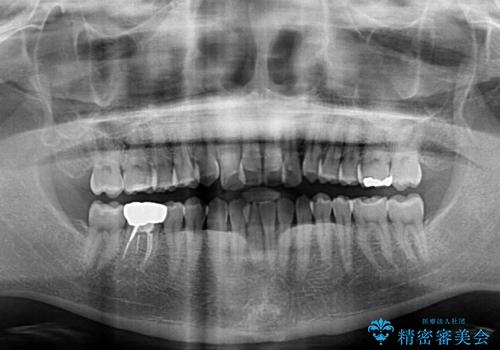

- 前歯のデコボコを治したいとのことで来院された患者様です。

上下顎ともに歯列全体の後方移動とIPR(歯と歯の間を削る)によってデコボコが解消するように設計し、インビザラインにより治療を行うこととしました。